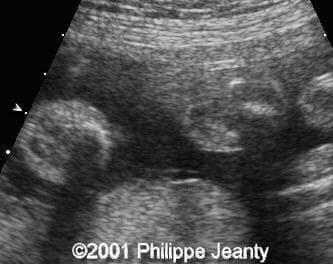

Note the striking cross-section of both lower legs with absence of the fibula on the right leg (left on the images):

clip0006

clip0007